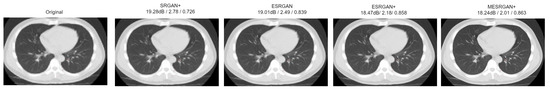

| Parameter | SRGAN | ESRGAN | ESRGAN+ | MESRGAN+ |

|---|---|---|---|---|

| Residual block of the generator | Conv(3, 64, 1) Batch norm ReLU Conv(3, 64, 1) Batch norm  | Conv(3, 64, 1) ReLU Conv(3, 64, 1)  | Conv(3, 64, 1) ReLU Conv(3, 64, 1)  | Conv(3, 64, 1) ReLU Conv(1, 64, 1) ReLU Conv(3, 64, 1) ReLU Conv(3, 64, 1)  |

| Input size | LR | LR | LR | LR |

| PSNR | 19.28 dB | 19.01 dB | 18.47 dB | 18.24 dB |

| Perceptual Index | 2.78 | 2.49 | 2.18 | 2.01 |

| SSIM | 0.726 | 0.839 | 0.858 | 0.863 |